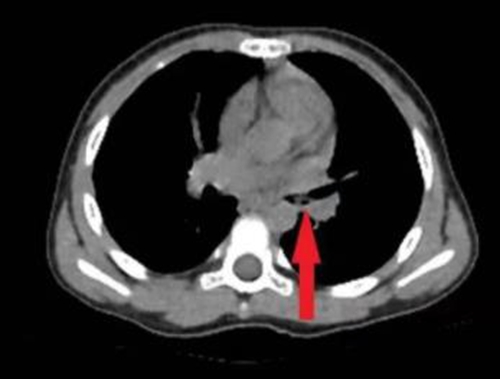

接诊医生询问孩子病史,为其完善胸部CT、重建气道,明确异物位置,发现小雨的左侧支气管内有异物。